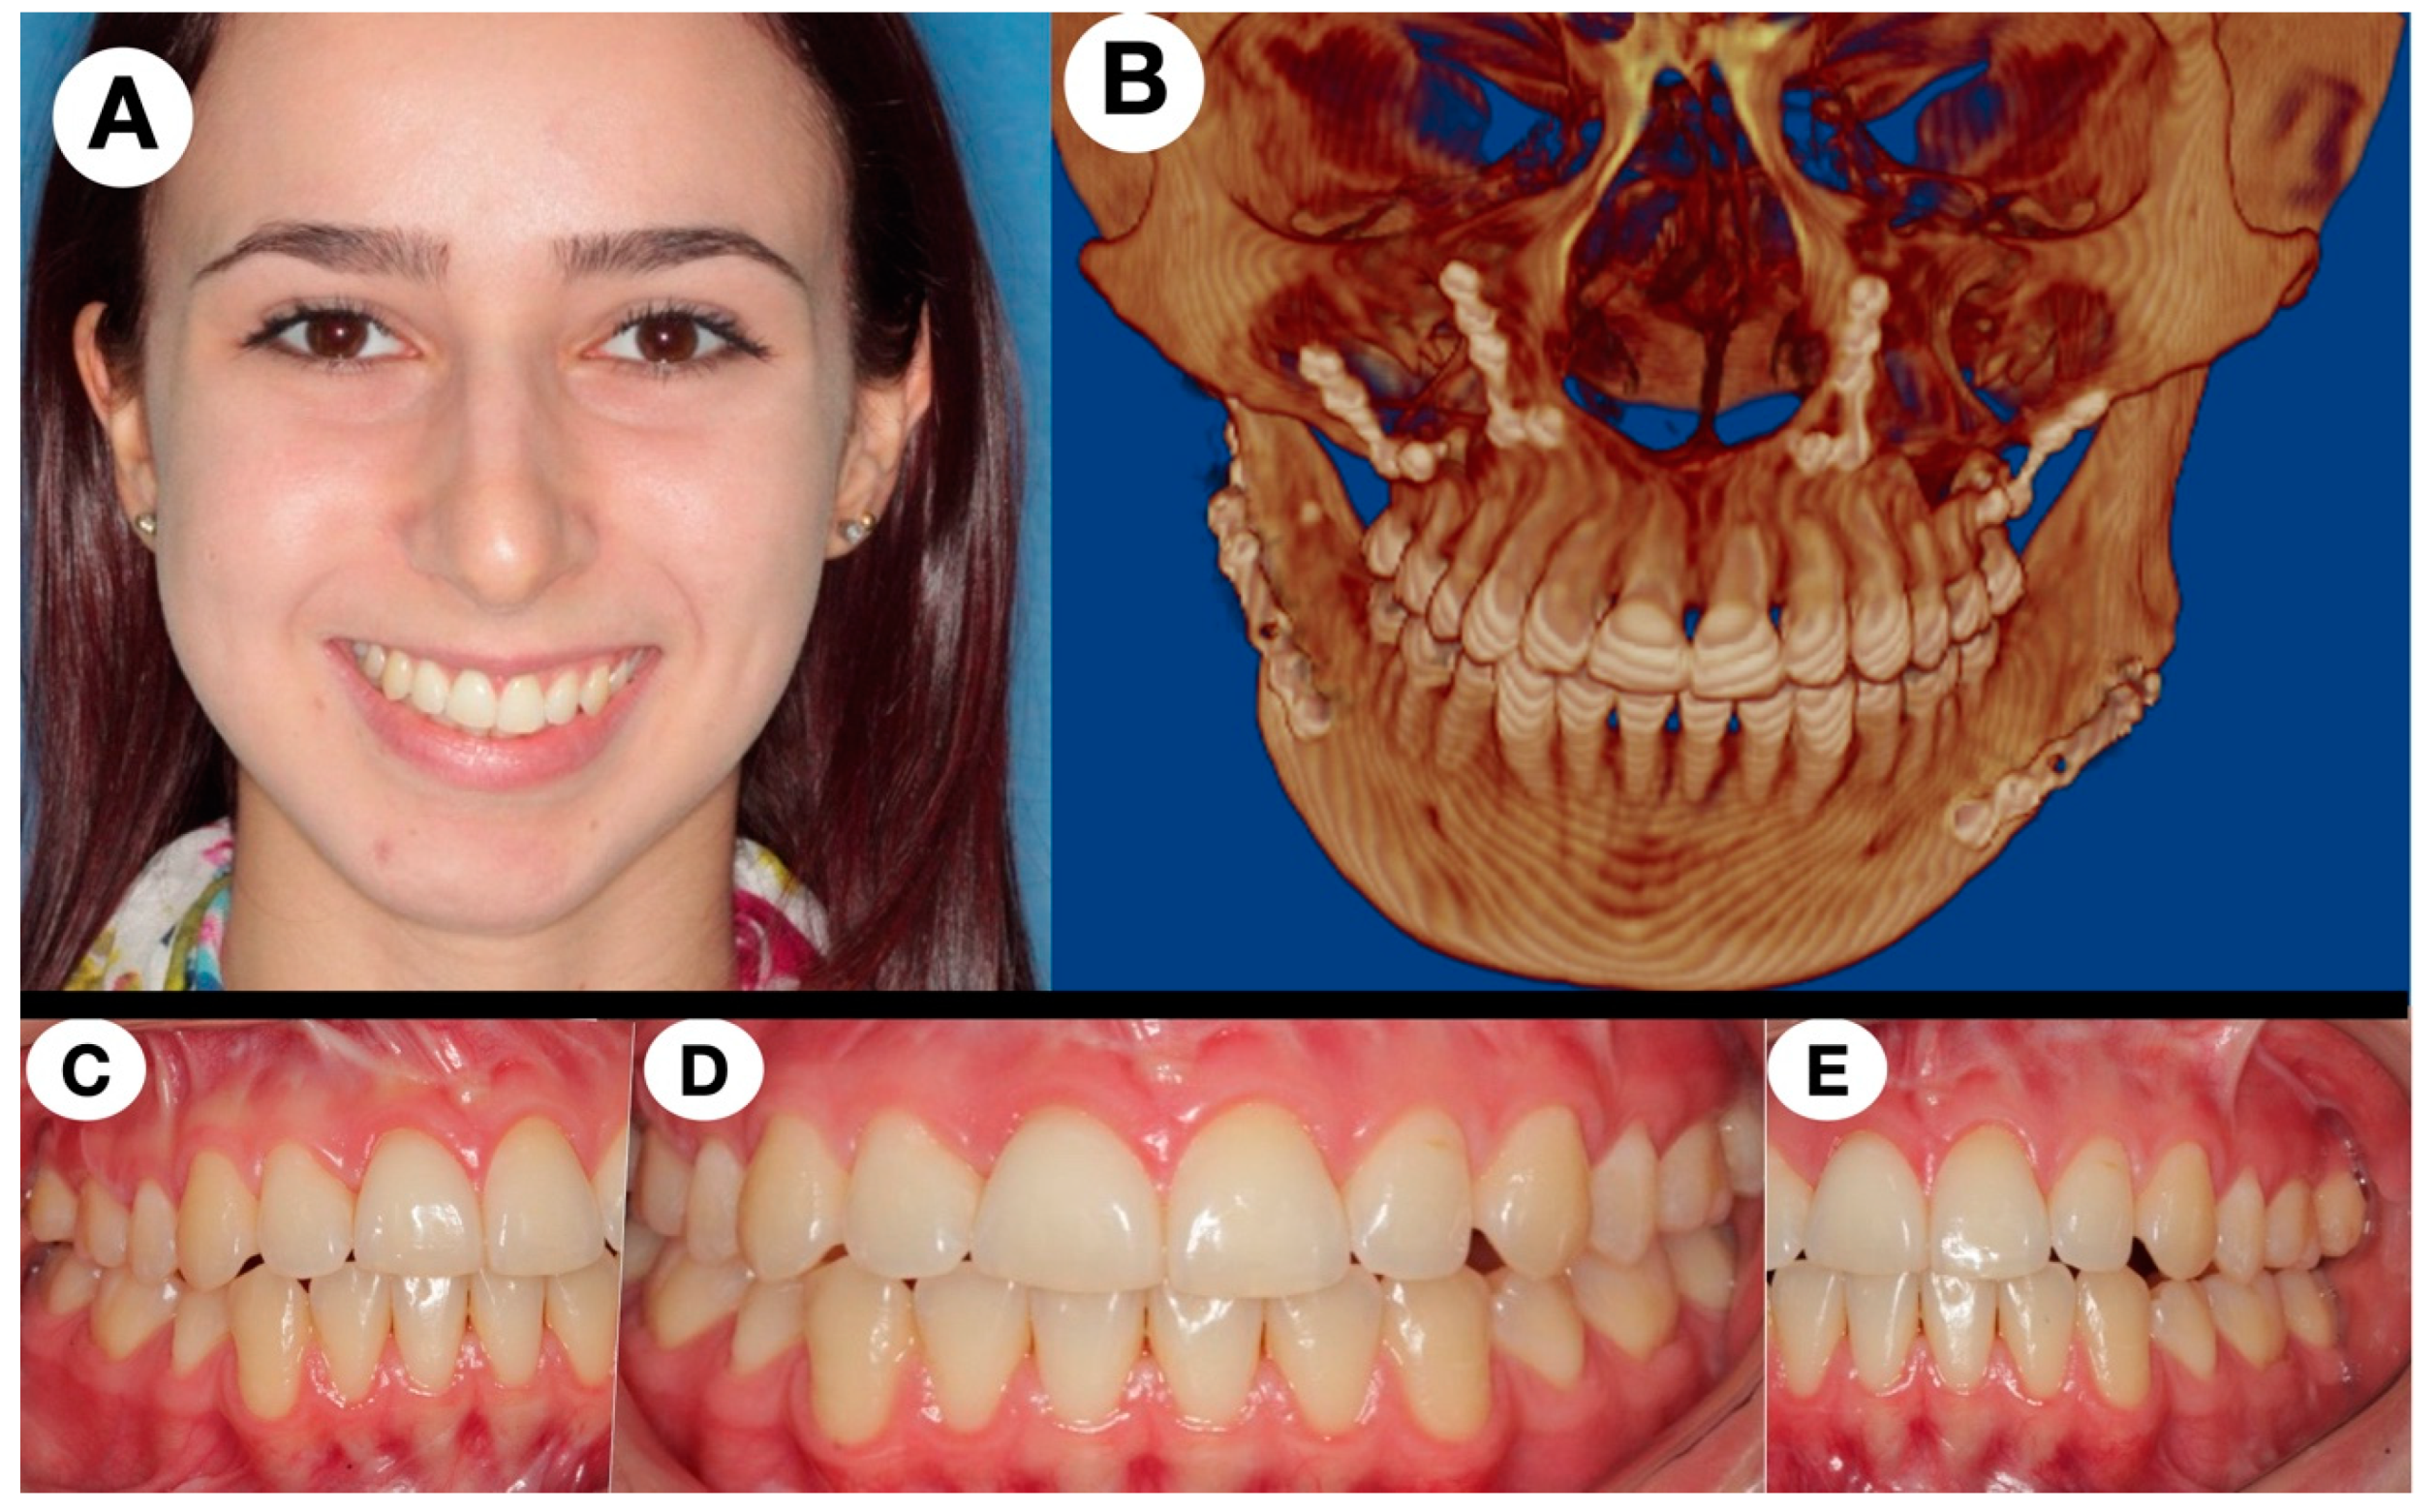

| Present case | 11/F | No swellings, joint pain during mandibular motion (1 year) | Well-defined radiolucent lesion on the right mandible head | Resection + sliding vertical ramus osteotomy + later orthognathic surgery | 13 years NRD |